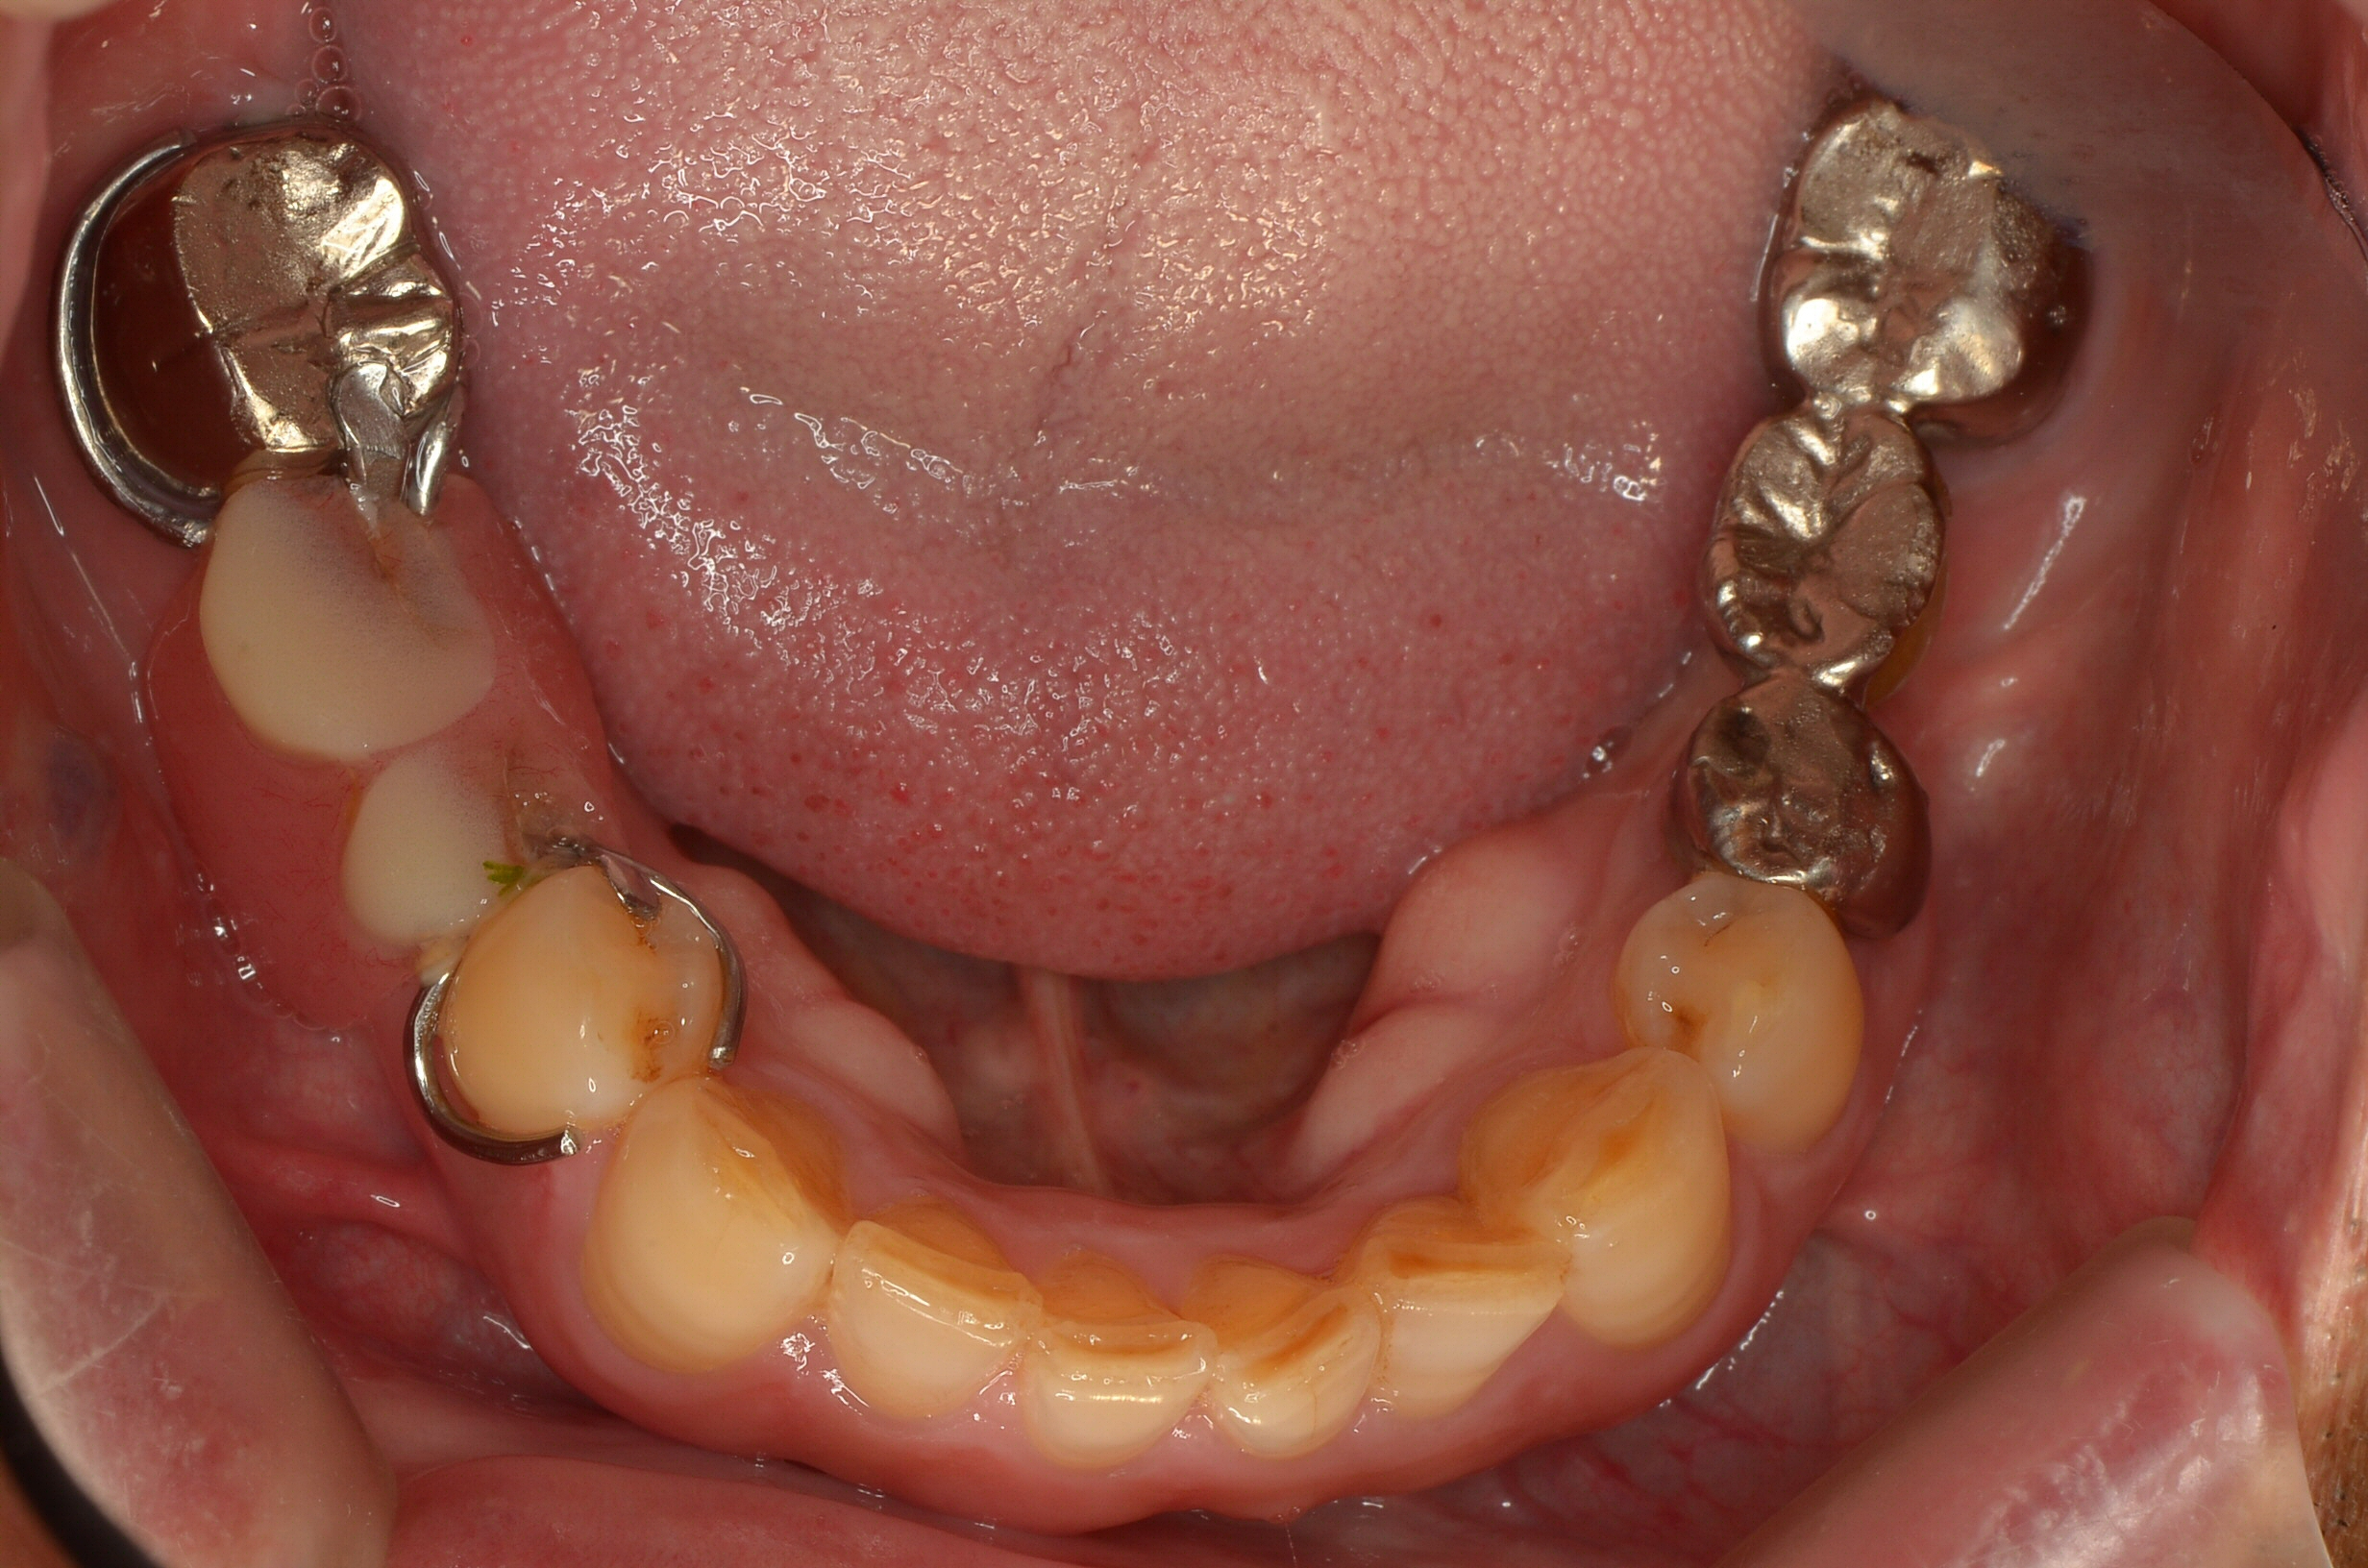

治療前

治療後

| 年齢 | 65歳 |

| 主訴 | 奥歯で硬いものが噛めない |

| 治療期間 | 約6ヶ月 |

| 治療費 | 約1,500,000円(分割ローン:15,000円〜) |

| 概要 |

奥歯で固い食べ物が噛めず、年齢とともに噛み合わせや咀嚼機能の低下を実感されていました。 |

| リスク | 外科手術を伴うため、腫れや痛み、内出血が生じる場合があります。 骨量が不足している場合、骨造成(GBRやソケットリフト等)の追加処置が必要となることがあります。 インプラントが骨と結合しない場合、再手術や撤去が必要となることがあります。 メンテナンス不足や清掃不良により、インプラント周囲炎(歯周病のような症状)が起こる可能性があります。 喫煙・全身疾患・噛み合わせの状態により、治療結果に影響が出る場合があります。 長期的な安定のためには、定期的なメンテナンスとセルフケアが必須です。 |